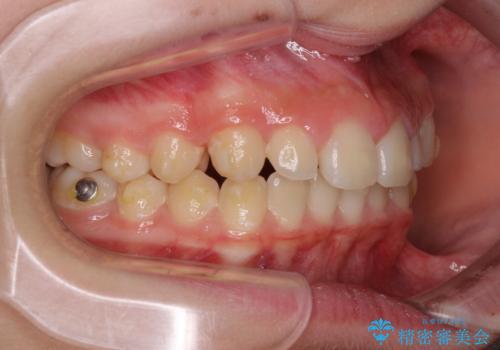

- ヨーロッパにてインビザライン矯正を始めたものの、日本に転居することになり、治療の継続を希望して来院された患者様です。

治療計画に無理がなく、現地担当医と速やかに連絡が取れるとのことで、インビザライン社での転医手続きを行い、継続して治療を行うこととしました。

舌の突出癖により、上下前歯が非接触となっていたため、トレーニングを徹底的に指導し、安定した咬み合わせにより終了させることができました。